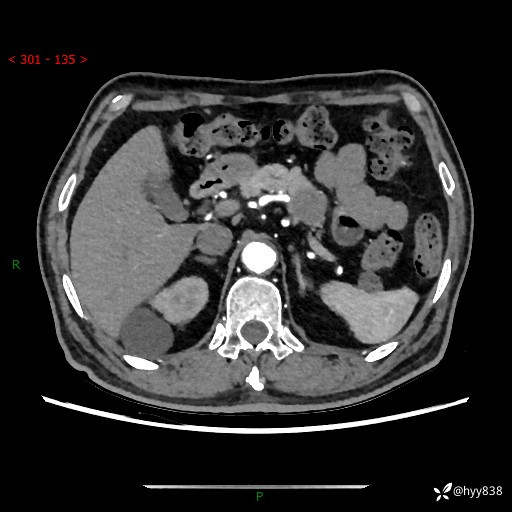

69岁/男,四肢无力3月余。胰腺囊实性占位,渐进性强化---结果公布~

【患者信息】:69岁/男

【主诉】:四肢无力3月余。

【现病史及既往史】:患者3月前无明显诱因出现四肢乏力,伴有口干、多饮、多尿等症状,无畏寒、发热、恶心、腹痛、腹泻等其他症状,于2024-06-13来我院住院治疗,完善相关辅助检查后,考虑“2型糖尿病”,予以降糖(阿卡波糖片 50mg po tid、德谷门冬双胰岛素注射液 8iu 早餐前 皮下注射)等治疗,口干、多饮、多尿较前缓解,血糖控制可;现仍存在四肢乏力,于2024-08-28来我院门诊就诊,查血钾2.88 mmol/L ,现以“低钾血症”收入我科。 本次起病以来,患者精神、饮食、睡眠良好,二便正常,近3月余体重下降约5kg。

【检查】:胰腺CT平扫+增强